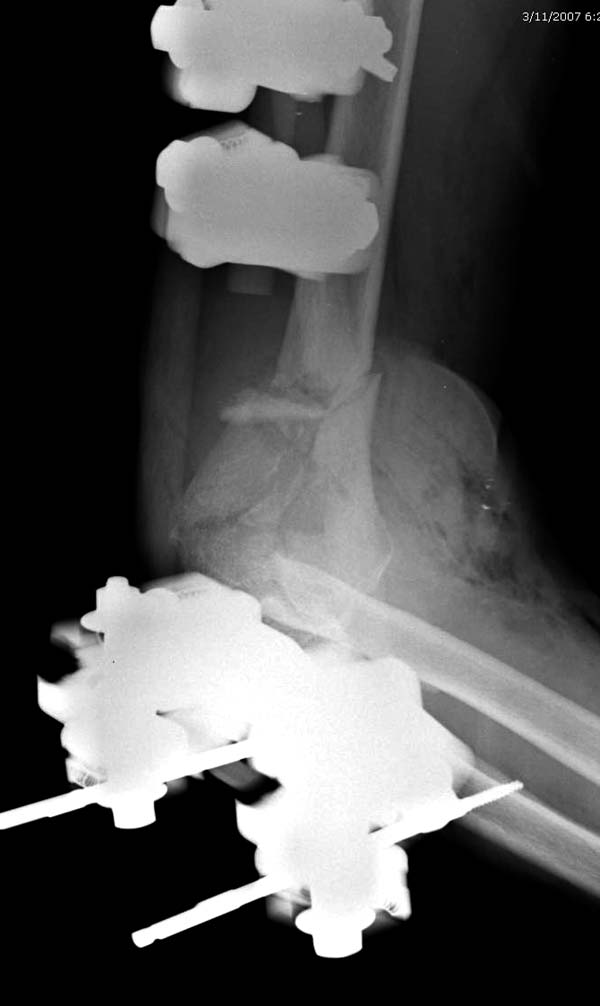

Примеры: первому более 15 лет фиксирован шурупом и tension band

technique, а второй перелом открытый больной 80 лет, после наружного

фиксатора в первом этапе и окончательная фиксация вторично. Третьий раз

внесуставная остеотомия...

Вложение не в текстовом формате было извлечено&hellip;

Имя     : 2-2 Distal Humerus.jpg

Тип     : image/jpeg

Размер  : 43412 байтов

Описание: отсутствует

Url     : http://weborto.net:8080/pipermail/ortho/attachments/20130604/c45a379f/attachment-0021.jpg